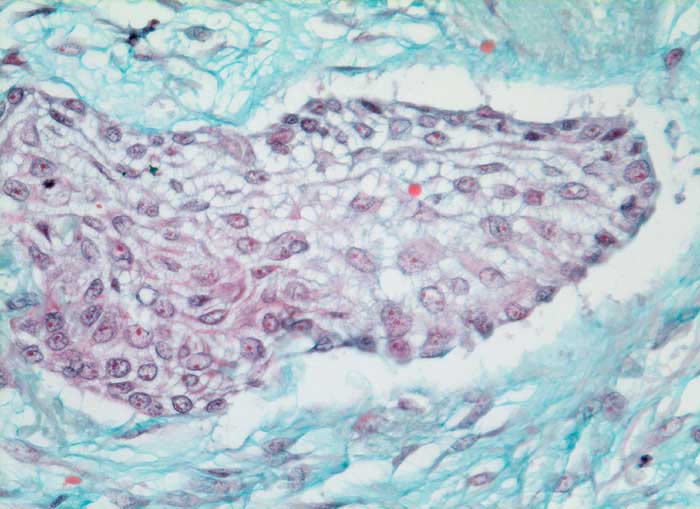

Verhornende Plattenepithelkarzinome sind charakterisiert durch mehr einzeln gelagerte Zellen mit deutlicher Pleomorphie, das Zytoplasma ist dicht und orangeophil. Die Kerne sind pyknotisch oder erinnern an Lavabrocken.

Die häufigeren nicht verhornenden Plattenepithelkarzinome bilden eher Verbände. Die Tumorzellen sind uniformer, das dichte Zytoplasma ist blau-grün gefärbt und scharf begrenzt. Die Zellkerne sind hyperchromatisch und enthalten grosse Nukleolen. Die Abgrenzung des nicht verhornenden Plattenpithelkarzinoms vom Adenokarzinom kann schwierig sein. In der Regel ist das Kernchromatin der Plattenepithelkarzinome dichter und die Nukleolen weniger prominent.

Die Abbildungen zeigen ein verhorntes und ein unverhorntes Plattenepithelkarzinom zum Vergleich.